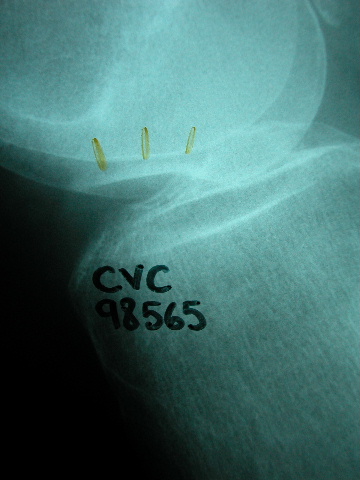

Tratamiento de fractura de radio con agujas.

Tratamiento con agujas de fractura de radio.